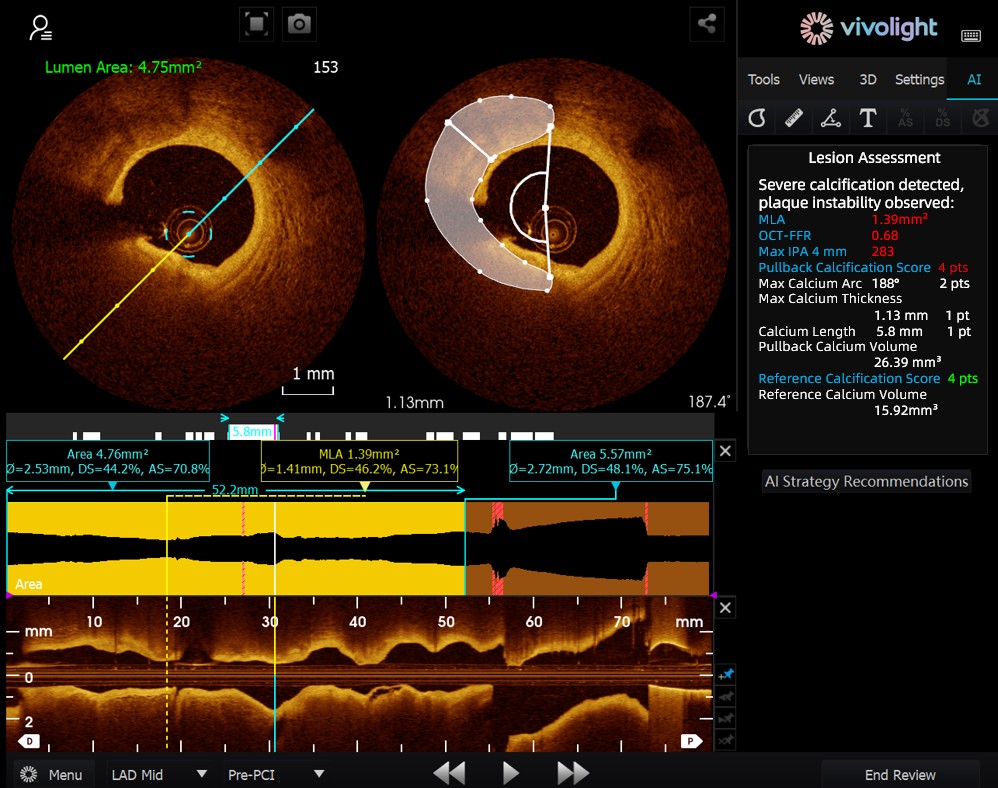

Developed based on Vivolight Medical’s OCT system, the AI-OCT is a next-generation intelligent decision-support system for intravascular imaging. It integrates scattered intravascular imaging diagnostic data—including lumen diameter, culprit lesions, OCT-FFR, and plaque natures—into comprehensive treatment strategies and actionable recommendations. As an independent research software embedded in the OCT platform, it is co-developed with various hospitals to create customized versions tailored to specific clinical needs.

During the cutting-edge forum, experts emphasized that AI-OCT System represents a transformative shift from "viewing images" to "delivering treatment plans"—addressing the challenges of information overload and complex decision-making in cardiac interventional procedures, which traditionally rely heavily on physician experience. Key advantages of the system include:

● Real-time Intraoperative Guidance: It dynamically organizes diagnostic information during surgery, providing key metrics and clinical recommendations.

● Evidence-based Decision-Making: All suggestions align with expert consensus and clinical guidelines, ensuring rigor and reliability.

The AI-OCT System adopts a "small model + big data + large model" architecture: small models enable precise image interpretation, while large models drive comprehensive clinical reasoning. Leveraging high-quality cardiovascular databases and Retrieval-Augmented Generation (RAG) technology, it delivers end-to-end support from lesion assessment to treatment strategy development.